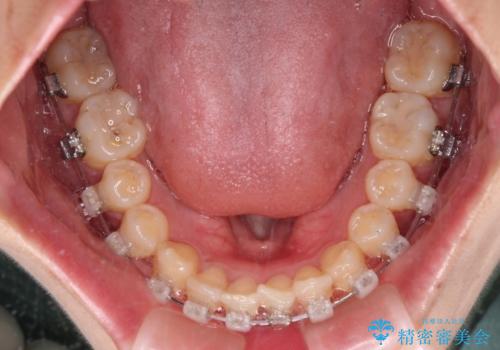

深い咬み合わせとデコボコの歯列をワイヤー矯正で改善

- 前歯のデコボコと深い咬み合わせを改善したいとのことで来院された患者様です。

奥歯の咬み合わせは上顎に対して下顎が後方位にあり、上顎前歯で下顎前歯が隠れるような典型的な過蓋咬合です。

補助装置を用いて上顎大臼歯を後方に移動させながら、ワイヤー装置で歯列を整えて深い咬み合わせを挙上することとしました。

下顎の装置が頻繁に脱落し、治療は難航しましたが、当初予定の2年間で無事に治療を終えることができました。